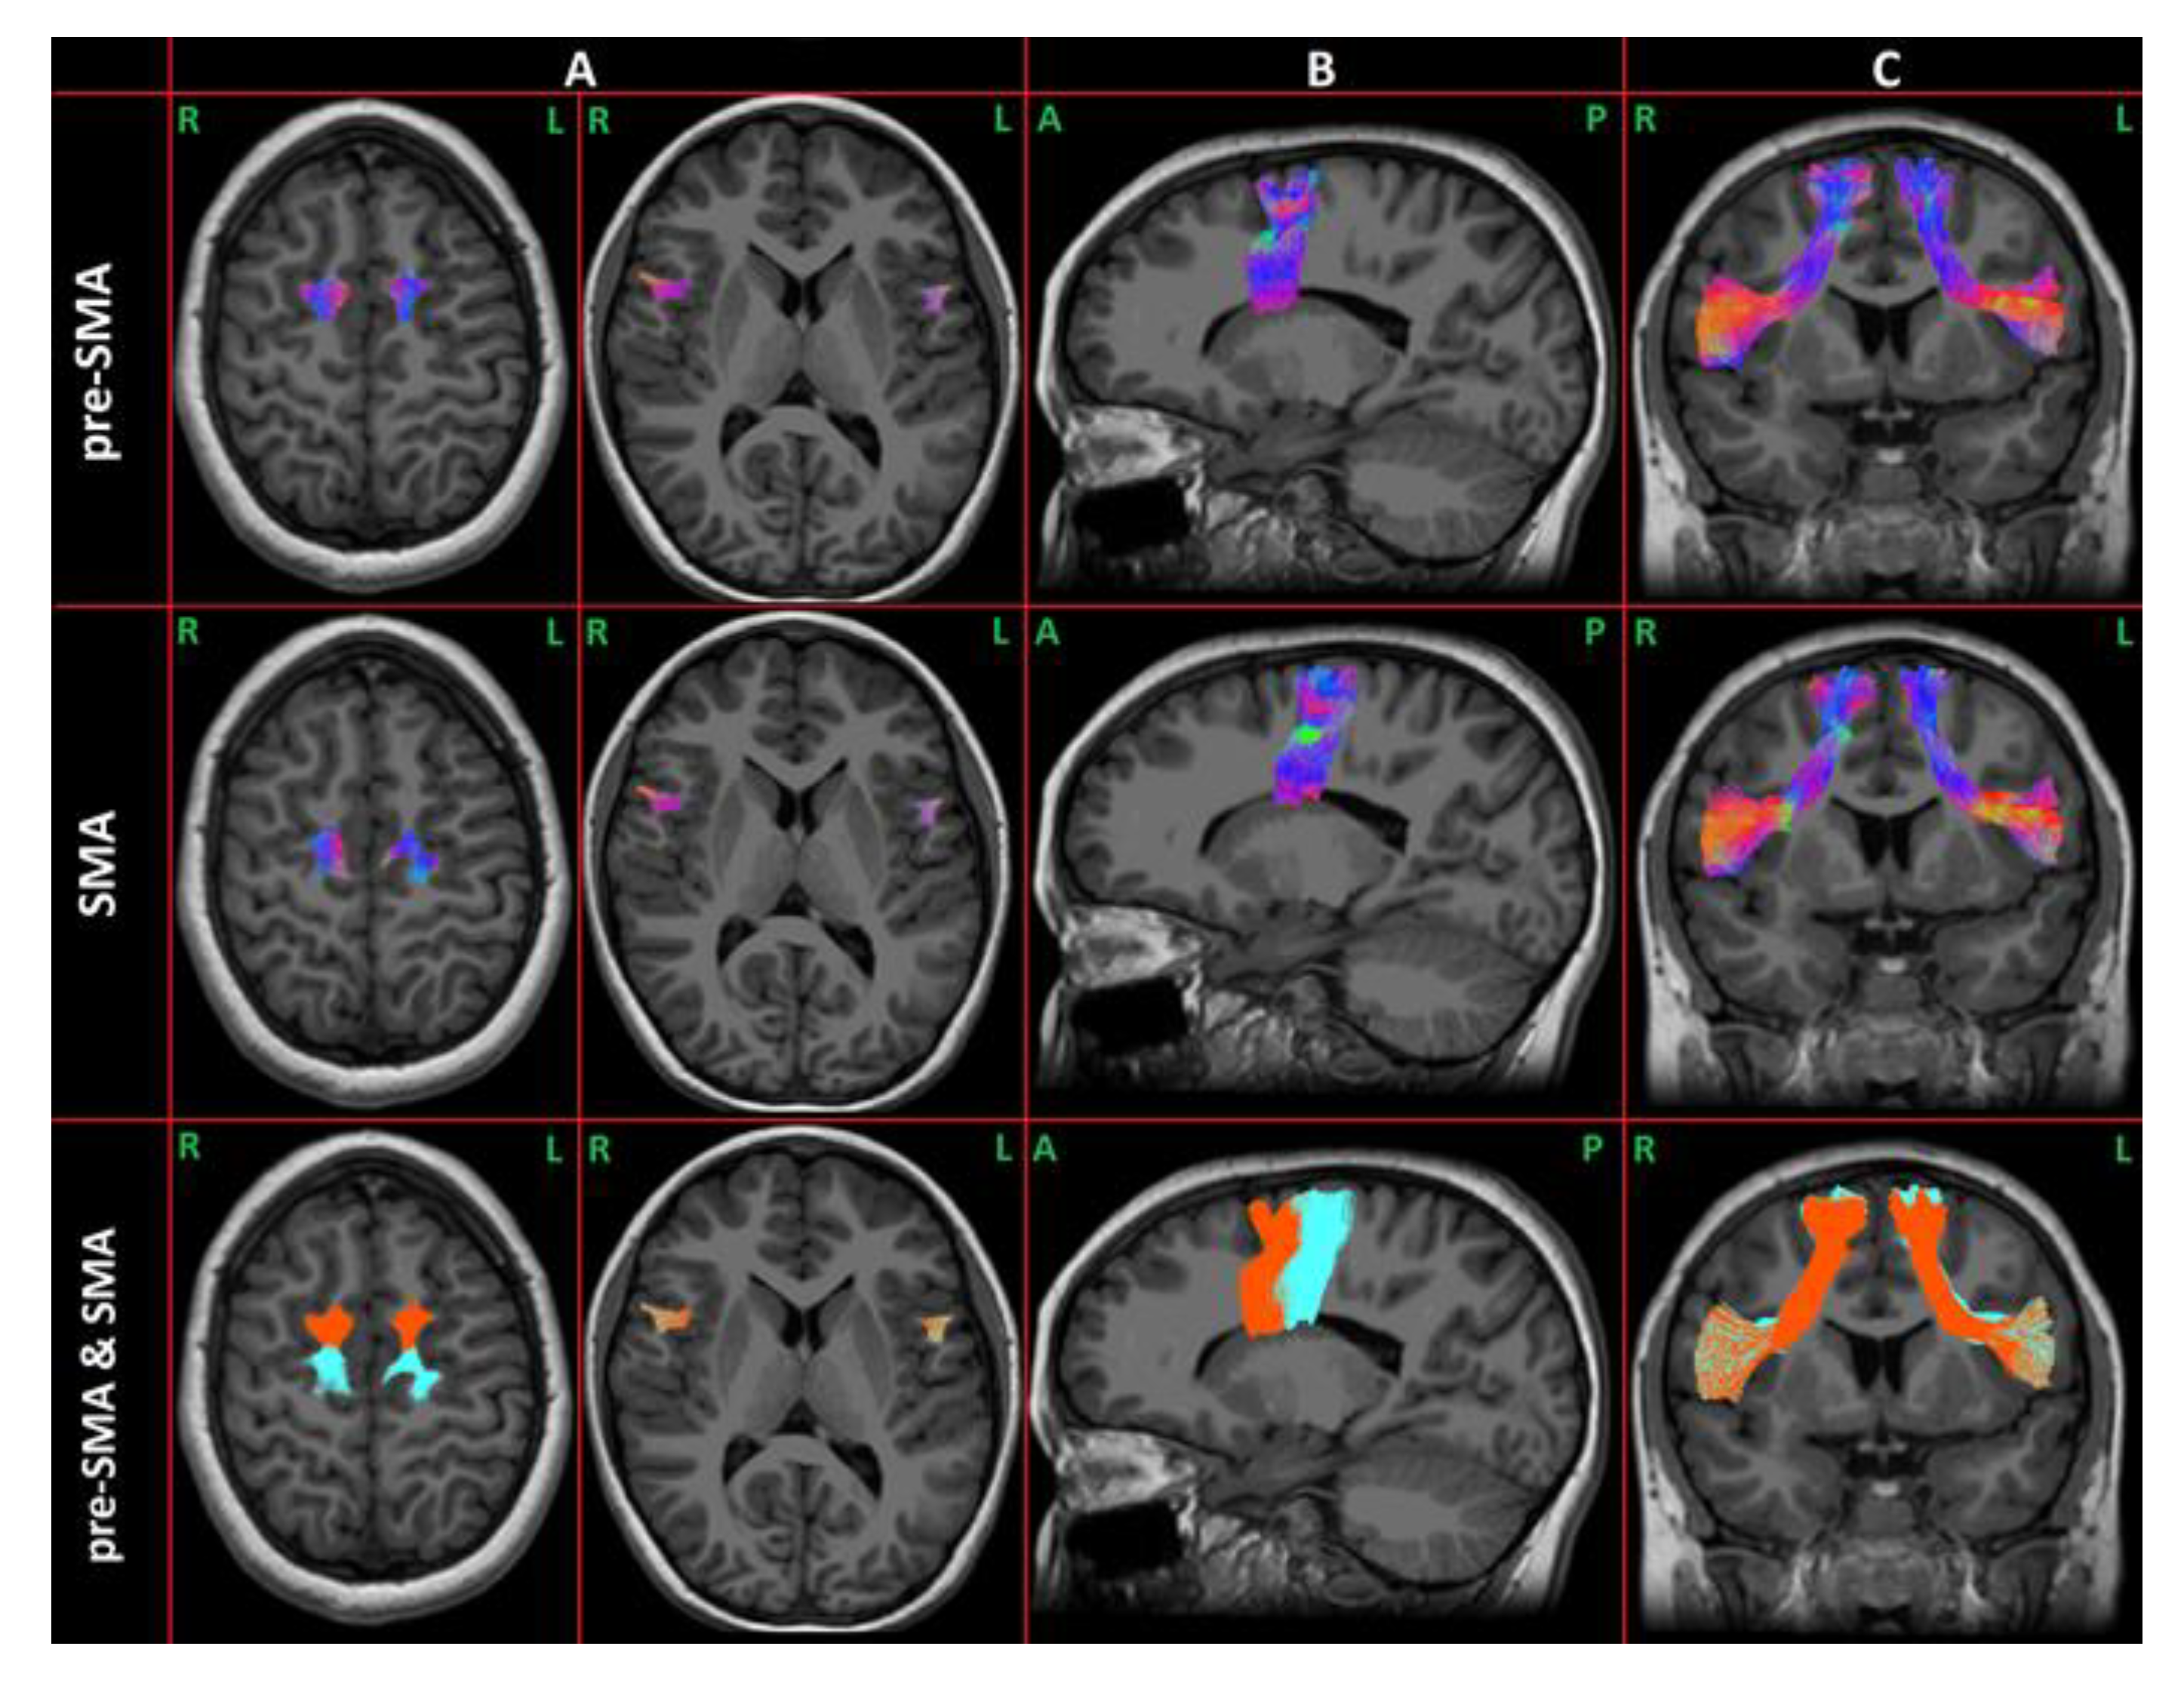

| FA-left preSMA FAT | 0.36 (0.02) | 0.39 (0.02) | 5.93 | 0.02 * |

| FA-right preSMA FAT | 0.37 (0.02) | 0.37 (0.03) | 0.01 | 0.90 |

| FA-left SMA FAT | 0.37 (0.02) | 0.39 (0.02) | 2.79 | 0.10 |

| FA-right SMA FAT | 0.37 (0.02) | 0.37 (0.03) | 1.71 | 0.19 |